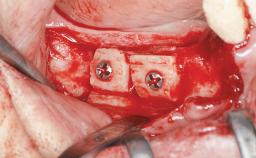

An 18-year-old man was referred for implant therapy in the posterior mandible to the Department of Oral Surgery and Stomatology (University of Bern, Switzerland). He was healthy and did not smoke. Tooth 35 was congenitally missing, involving a single-tooth edentulous space that offered an adequate mesiodistal dimension for implant placement but exhibited a typical pattern of buccal flattening. A panoramic radiograph was obtained, which revealed a sufficient vertical bone height above the mandibular canal and a normal bone structure in the edentulous area.